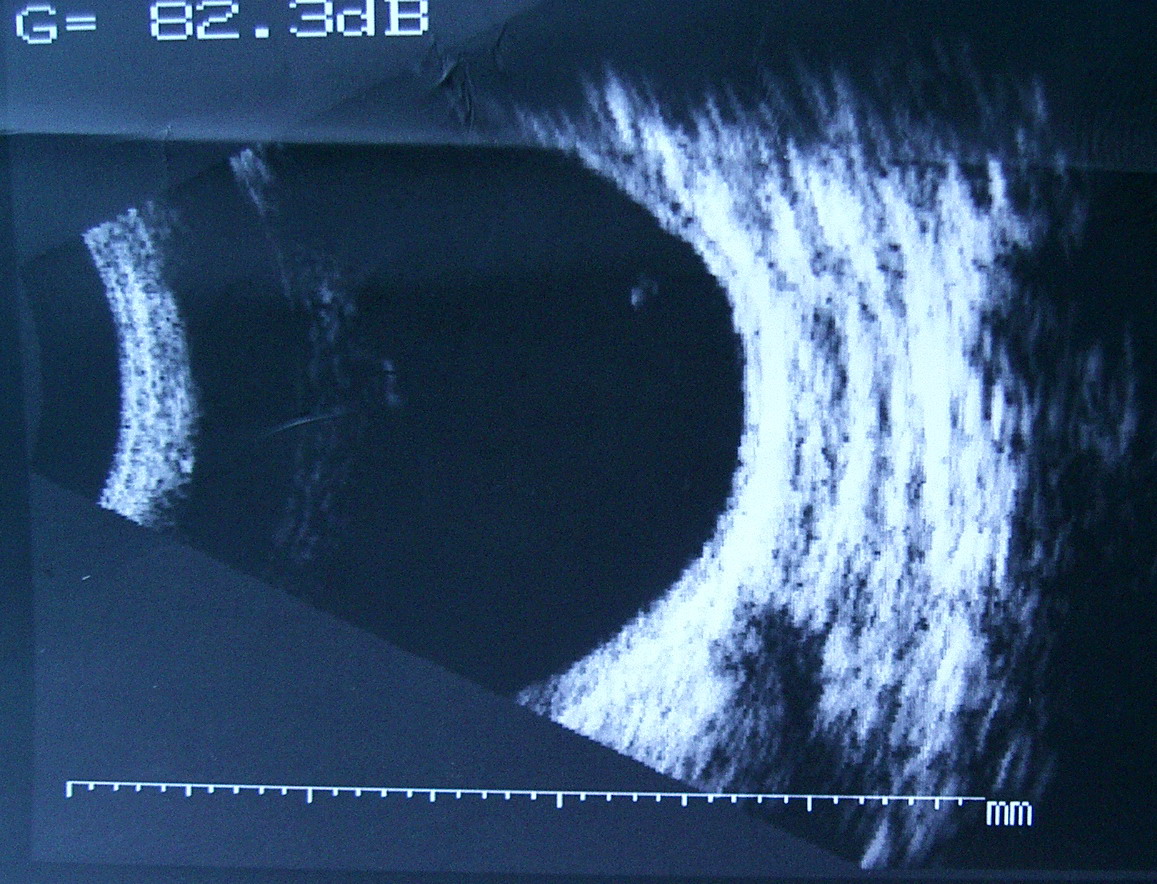

[B超]

此主题相关图片如下:

B超:

OD:眶未见明显异常回声区。

OS:眶鼻侧见边界不清,回声强弱不均之异常回声区。

意见:

右眼眶未见占位性病变声像。

左眼眶可疑占位性病变声像。建议CT进一步检查。